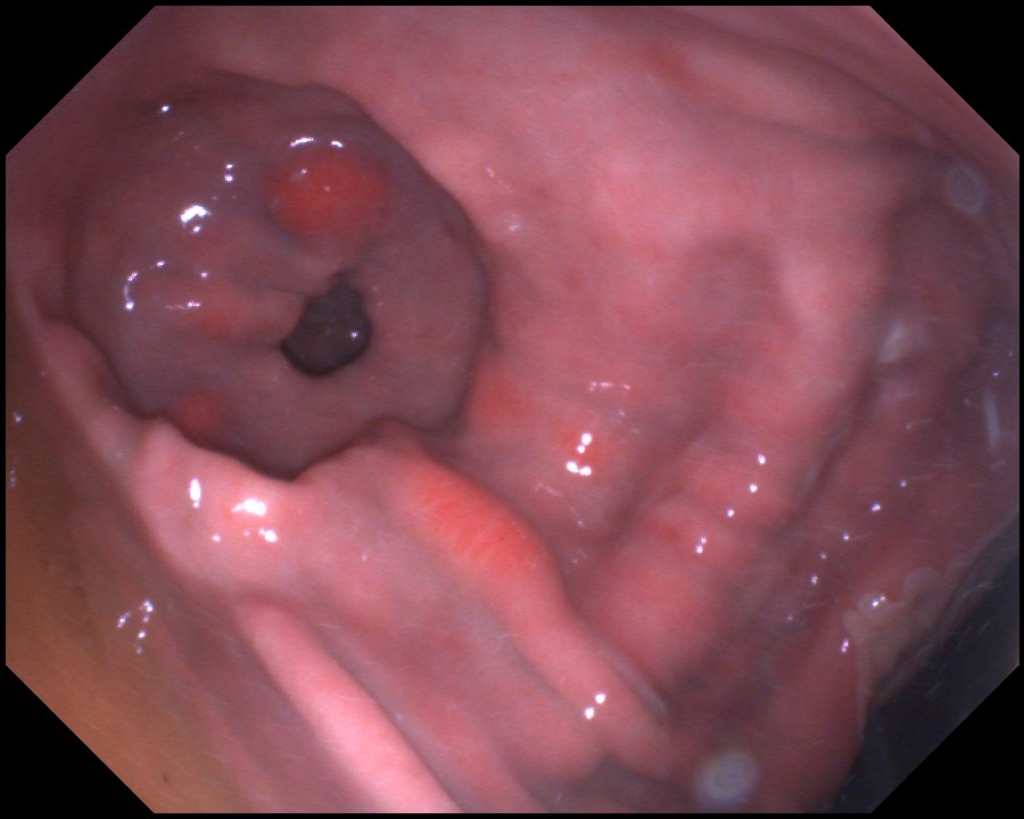

Maagzweren in het verhoornde deel van de maag en op de margo plicatus

Maagzweren in het verhoornde deel van de maag

Maagulcera net boven de margo plicatus

Maagzweer in het verhoornde deel van de maag, net boven de margo plicatus

Foto: Maagzweer in het verhoornde deel van de maag, net boven de margo plicatus